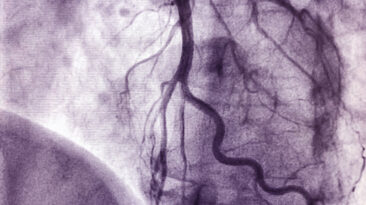

Eine Herzkatheteruntersuchung zählt zu den Routineeingriffen in der Kardiologie. Sie ermöglicht es, Durchblutungsstörungen, Herzklappenfehler oder...